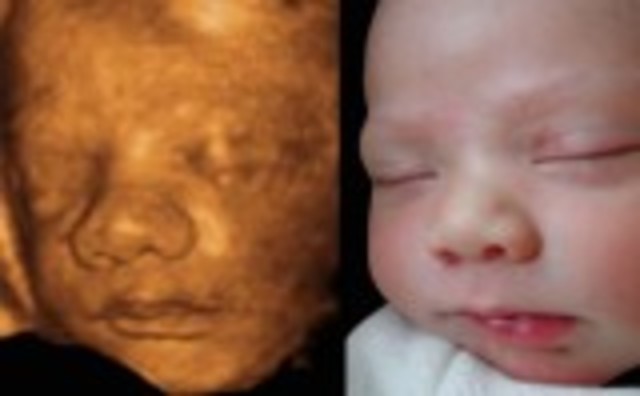

• Week Nineteen: Genitals recognizable

Week Nineteen: Genitals recognizable

the heartbeat can be captured on a ultrasound. you can tell wheither its a boy or girl.

• Week Twenty: The halfway point

Week Twenty: The halfway point

the baby can notice its moms voice. the hair start growing.

• Week Twenty Seven: Eyes can open

Week Twenty Seven: Eyes can open

Your baby's hearing continues to develop. The eyes can blink, open and close.

• Week Twenty Eight: May recognize your voice

Week Twenty Eight: May recognize your voice

The hair on the head is now clearly visible. The milk teeth have developed under the gums. The eyes are starting to move in their sockets.